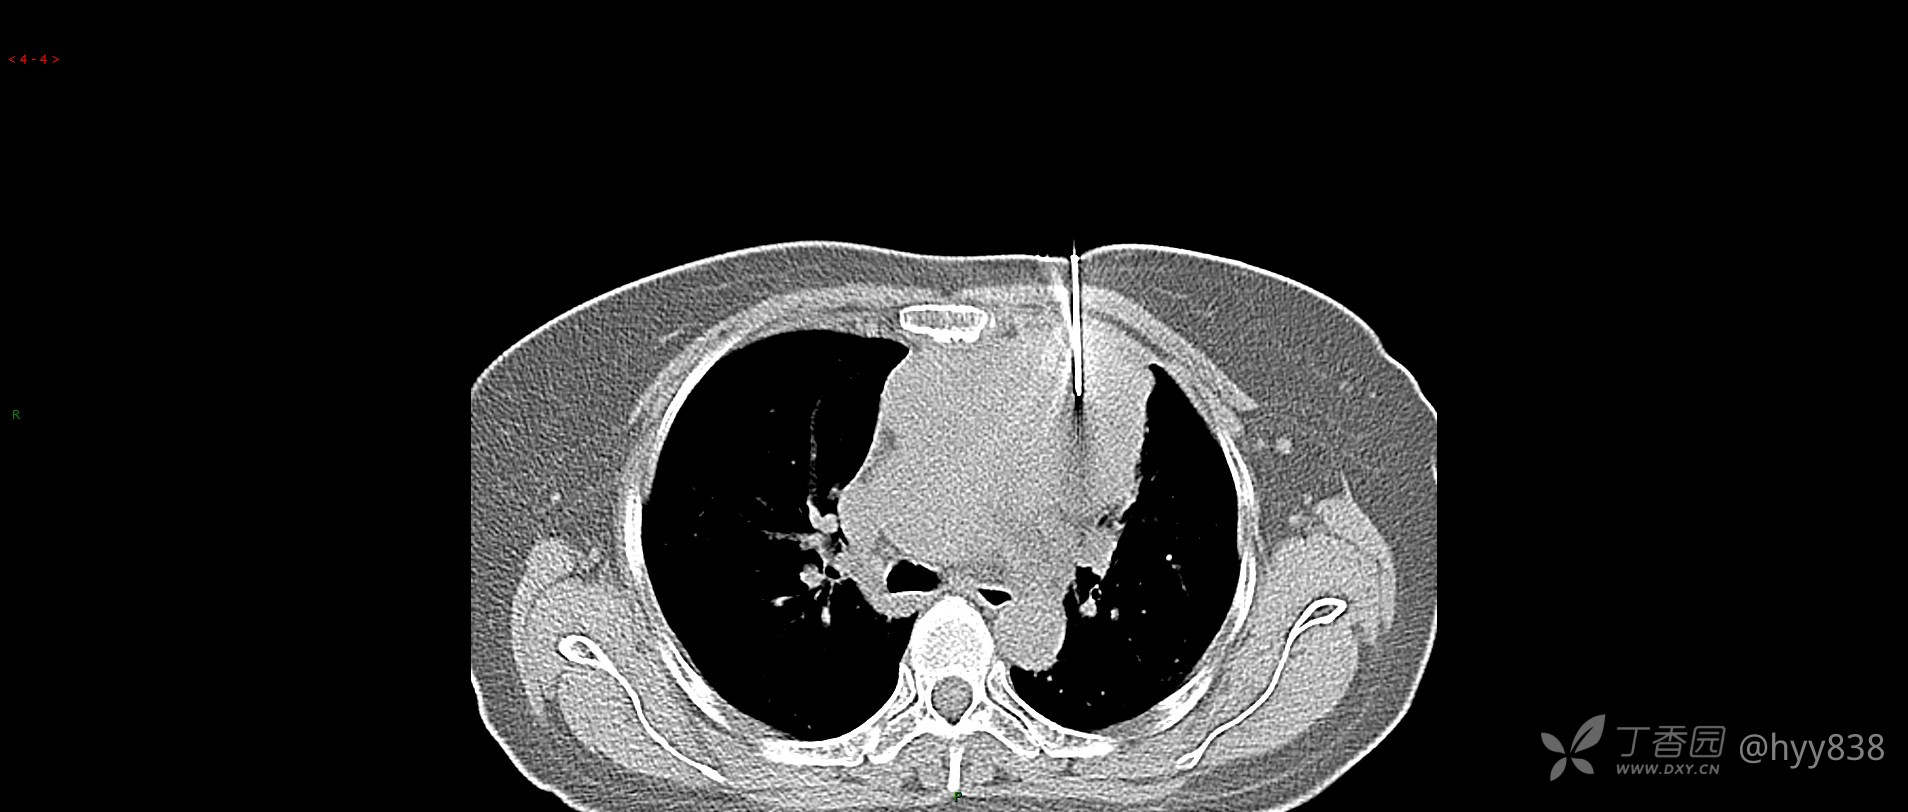

简要病史:患者诉3月余前患新冠肺炎,出现持续性胸闷,活动后可缓解,无胸前区压榨感,无畏寒发热不适,无胸痛咯血、呼吸困难,无恶心、呕吐,无腹痛、腹胀、腹泻等不适,未予以重视,未行特殊处理。患者胸闷持续存在,为进一步诊治,3天前于本院查胸部CT提示前纵膈团块状软组织密度影,肿瘤性病变可能,心包积液,左上肺磨玻璃结节,右下肺增殖灶可能建议进一步检查。门诊以“前纵膈占位” 收入我科。 患者本次起病来精神、食欲、睡眠尚可,大小便正常,体力、体重无明显变化。

辅助检查:CT

临床诊断:纵隔占位

胸部CT平扫

动脉期

静脉期

穿刺